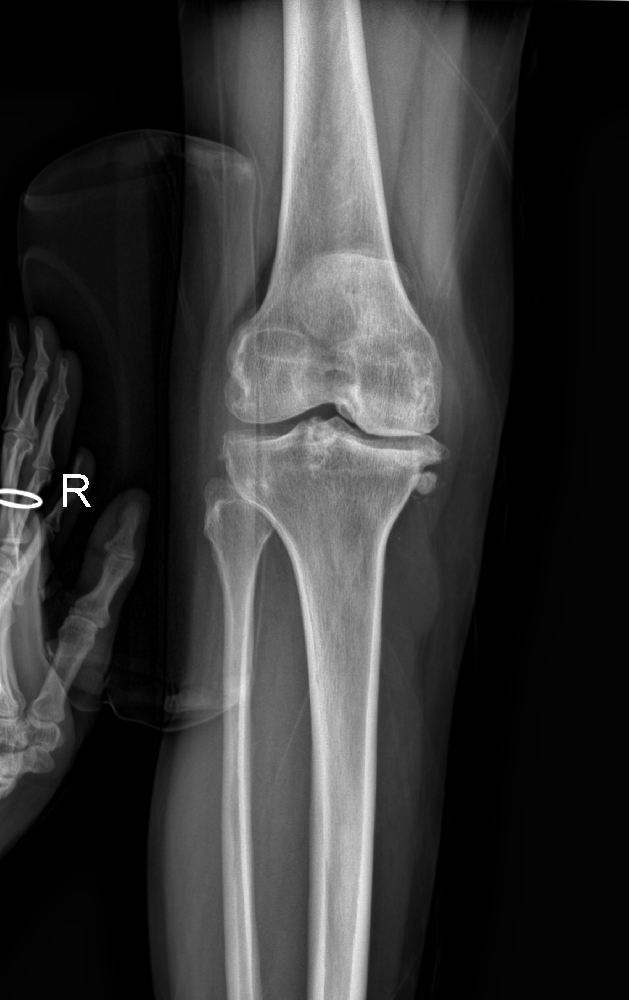

在薛城區(qū)周營鎮(zhèn)大孫莊村,有一位56歲的女性賈紀(jì)花,她身上散發(fā)出一種堅(jiān)毅和頑強(qiáng)面對疾病的氣息。這位女性已經(jīng)遭受右膝關(guān)節(jié)疼痛的困擾超過十年,但在經(jīng)過一場奇跡般的手術(shù)后,終于迎來了疼痛消失的好日子。

為了擺脫這長期的苦痛,賈紀(jì)花選擇了市中區(qū)誠德骨科醫(yī)院入院接受更為全面的檢查。在完成檢查后,醫(yī)生決定為她實(shí)施右膝關(guān)節(jié)內(nèi)側(cè)活動平臺單髁置換術(shù)。手術(shù)完成后,賈紀(jì)花術(shù)后恢復(fù)良好,再次嘗到了疼痛消失的滋味。